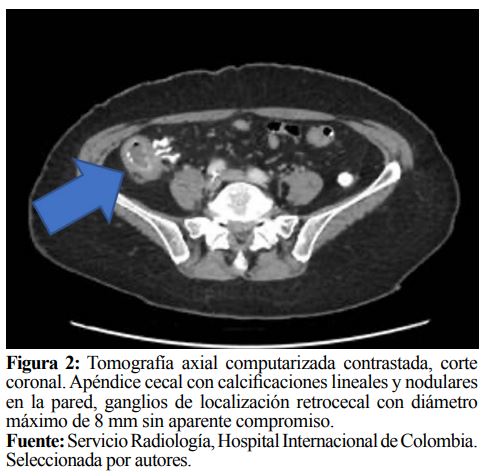

Paciente remitida a institución de mayor complejidad por sospecha de abdomen agudo. Fue valorada por el servicio de cirugía dada la persistencia del dolor abdominal en hemiabdomen inferior derecho, considerando manejo antiespasmódico y antiinflamatorio con respuesta analgésica favorable. El dolor se evaluó mediante la escala análoga y numérica del dolor. Se solicitó estudio complementario de tomografía de abdomen con contraste que mostró marcada dilatación quística del apéndice cecal con calcificaciones lineales y nodulares en la pared y en su interior, alcanzando un diámetro máximo sagital de 6 cm y diámetro transverso de 2.4 cm, sin presencia de edema de la grasa adyacente, ganglios de localización retrocecal con diámetro máximo de 8 mm sin aparente compromiso y presencia de leve ateromatosis aórtica (Figuras 1 y 2).

Generalmente, el diagnóstico definitivo se realiza mediante el estudio histológico de la pieza anatómica. Su manifestación clínica principal es asociada con apendicitis aguda, como en el paciente anteriormente presentado, por los hallazgos al examen físico en fosa iliaca derecha, sospechando inicialmente un abdomen agudo. En cuadros más avanzados su presentación clínica se caracteriza por distensión abdominal, dolor abdominal crónico, pérdida de peso, anemia, hernias umbilicales o inguinales y cuadros severos de obstrucción intestinal (9). En el estudio radiológico, la Tomografía Axial Computarizada es una herramienta útil, encontrando aumento difuso del apéndice, manteniendo su forma vermiforme con engrosamiento o dilatación de la pared y de los tejidos periapendiculares, lo que podría traducirse en inflamación periapendicular o infiltración linfomatosa (10). Lo anterior concuerda con los hallazgos tomográficos encontrados en el paciente del reporte de caso, además de la relación existente por ser una paciente femenina mayor de 50 años, cuya edad coincide con la población principalmente afectada por los tumores apendiculares.